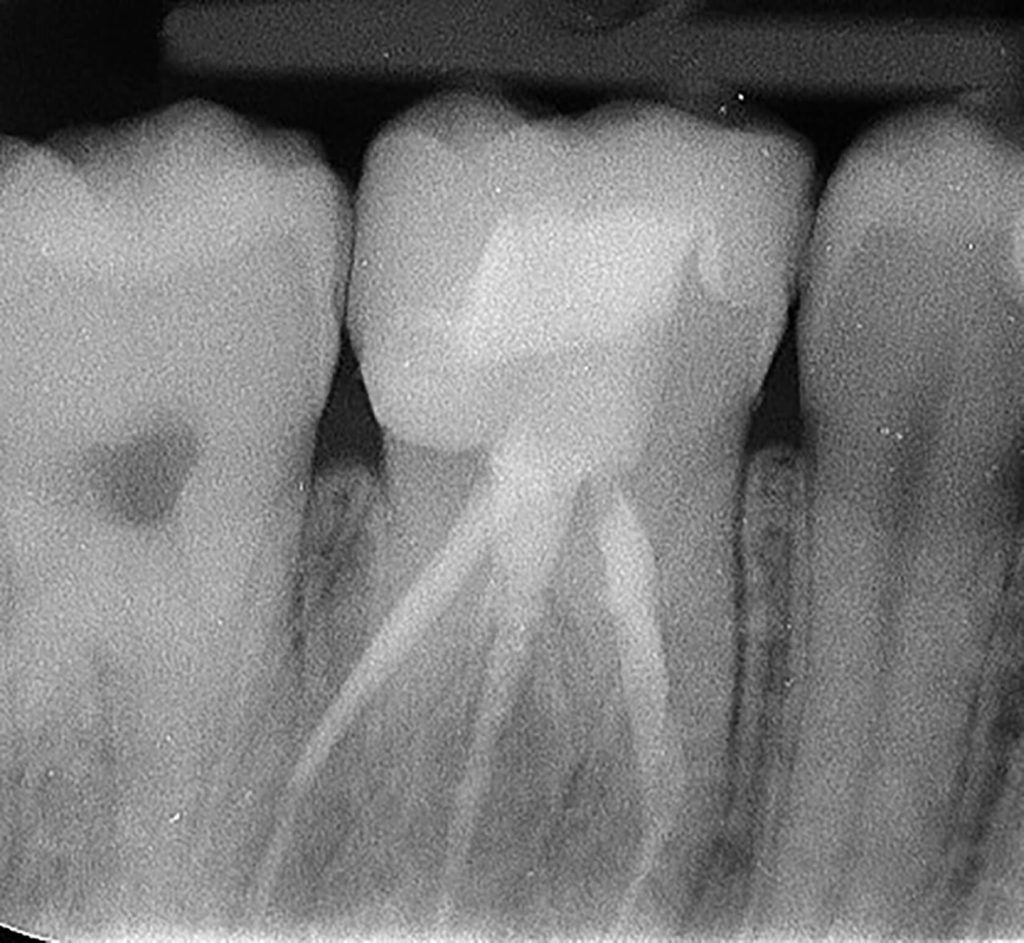

Patient presented with deep distal decay on first molar. Used deep margin elevation and papillectomy. No attempt was made to establish 3 mm biologic width space. Overlay prep and lithium disilicate indirect restoration placed. Photos from 15 month follow up included.